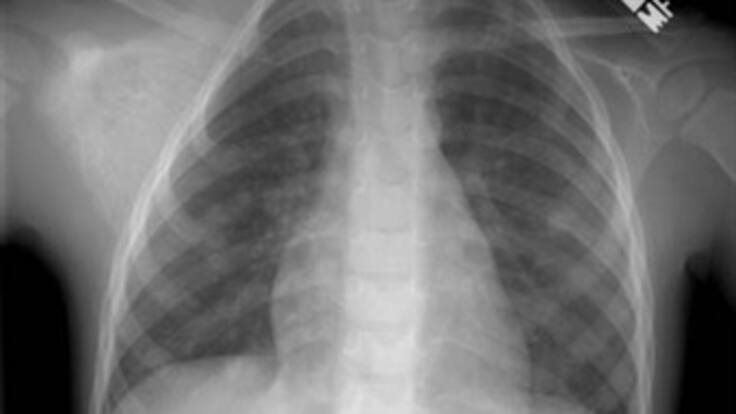

El dictamen médico dice que tiene un cuerpo extraño de considerable tamaño en el esófago. El menor, finalmente, fue remitido anoche a la Clínica del Caribe, donde le practicaron una endoscopia para ver si le pueden retirar la piedra

Después de este procedimiento los médicos lograron mover la piedra del lugar donde se encontraba buscando que el niño la expulse para luego seguir con la valoración del menor